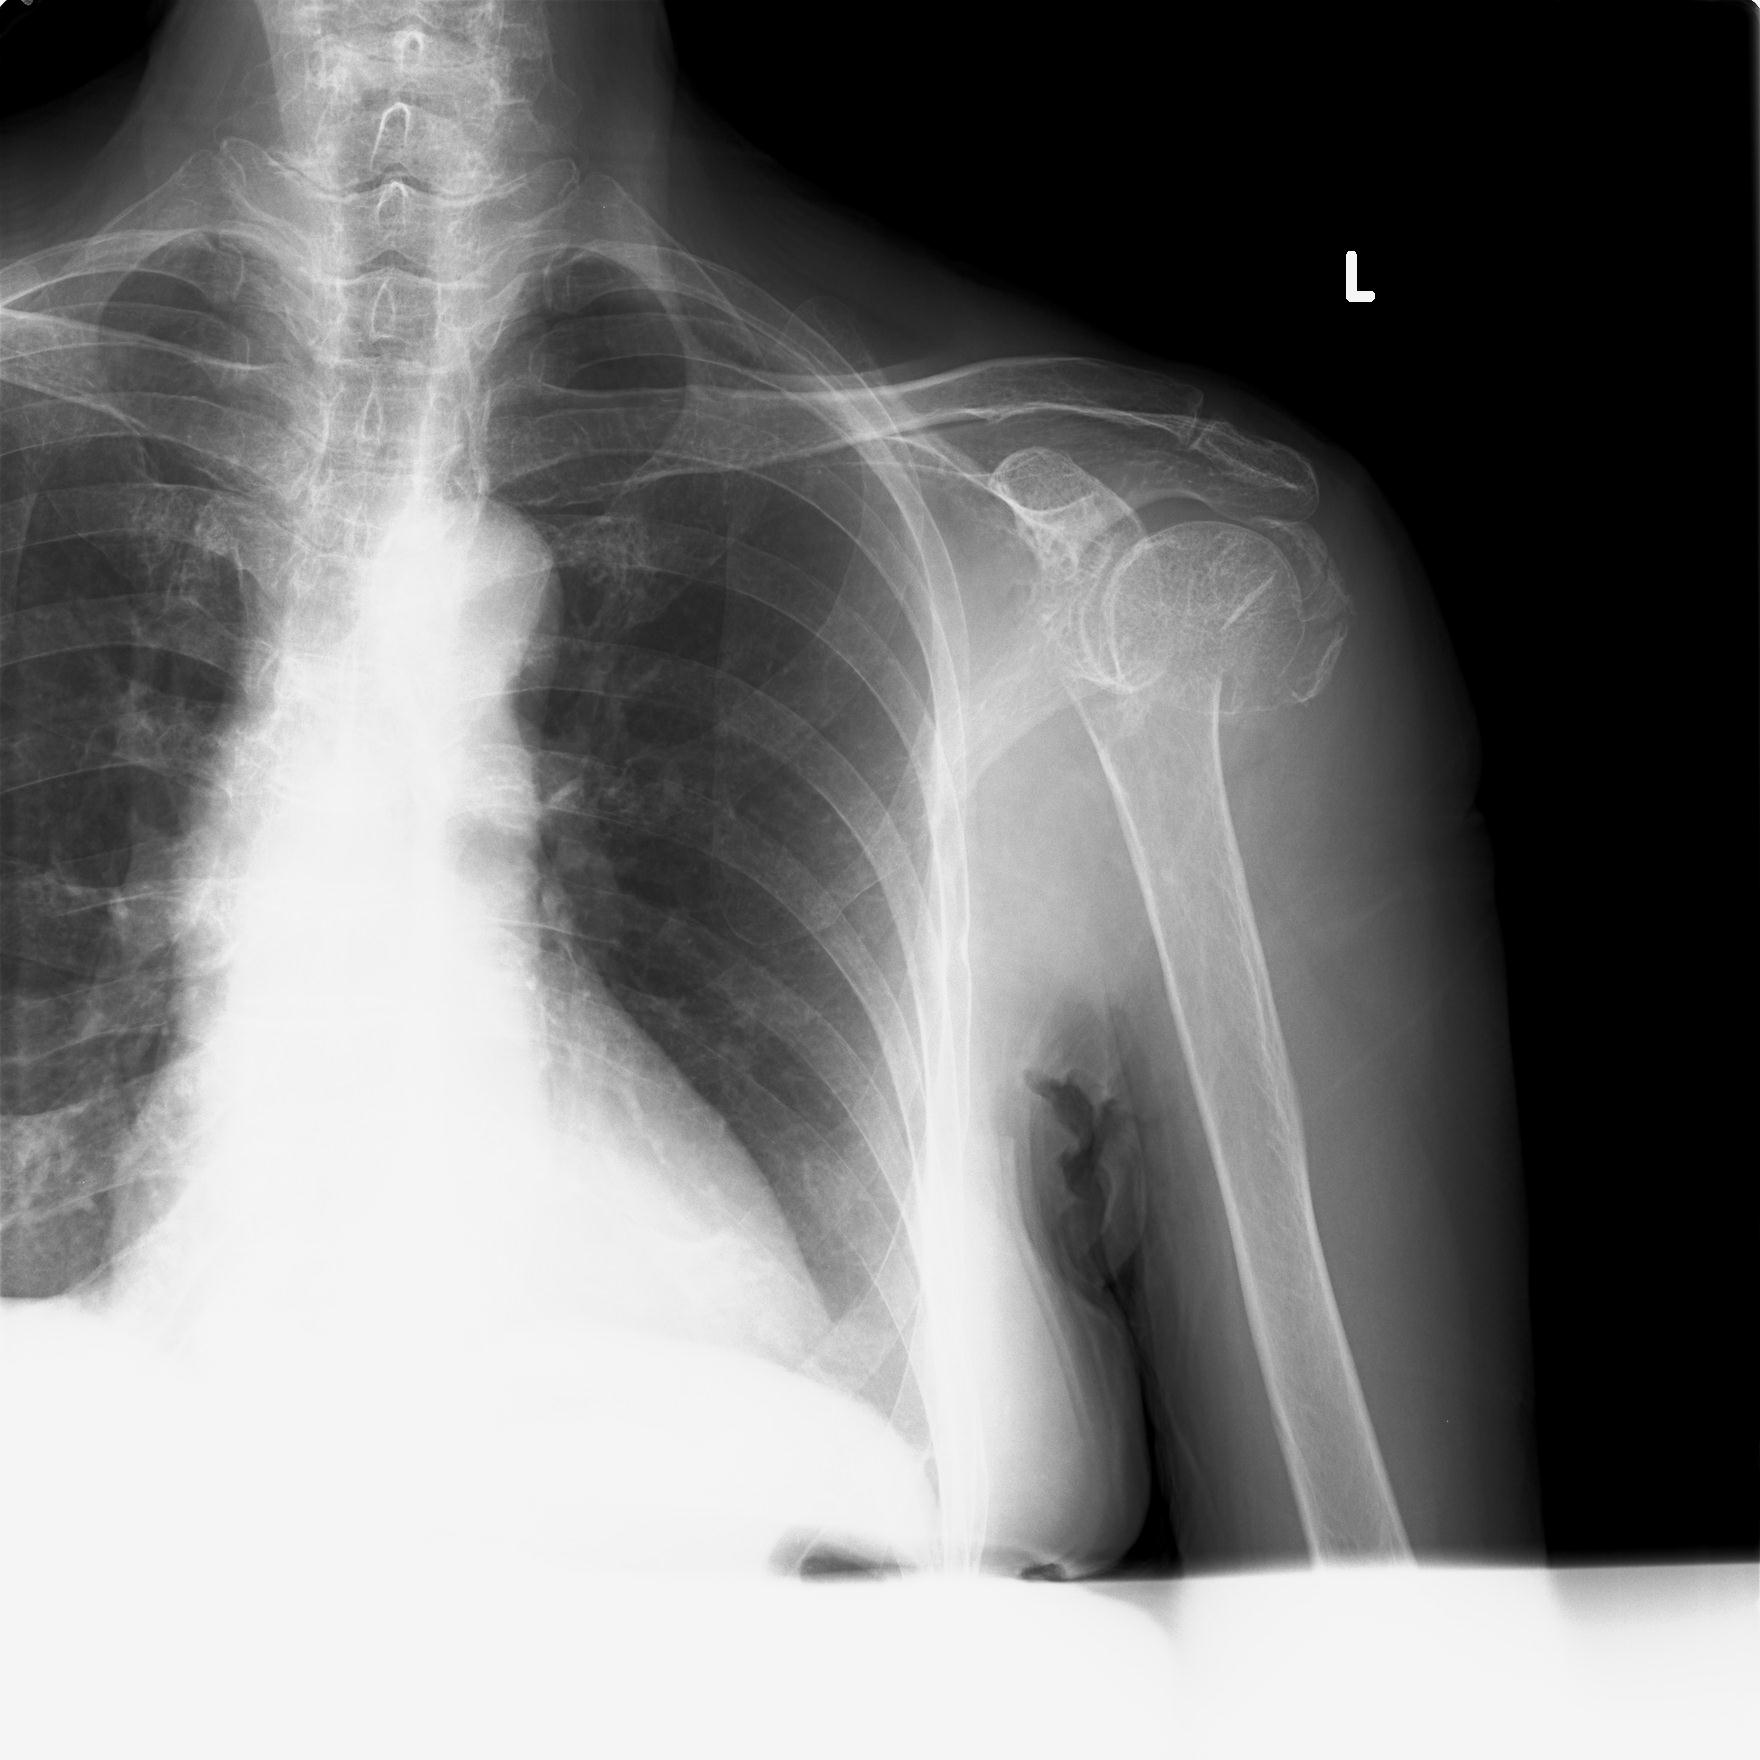

110214 12/20 肩 2R 12/21 肩 4R 72歳女性 左上腕外科頚プレート